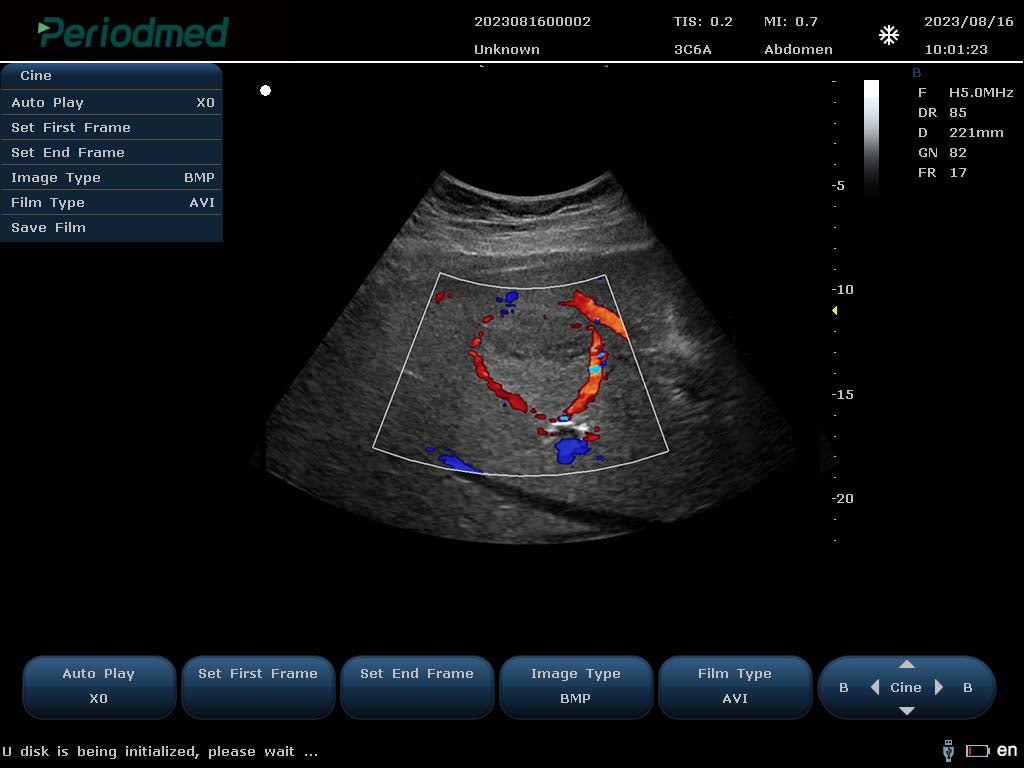

PU-L151B Portable Color Doppler Ultrasound by Yonker – Now at AdamsMed UAE & Africa (Powered by Periodmed)

Looking for a powerful and portable color Doppler ultrasound system? The PU-L151B by Yonker is the ideal diagnostic imaging solution for clinics, hospitals, and mobile healthcare providers. Now available through Periodmed and distributed by AdamsMed, this compact yet advanced ultrasound machine offers superior imaging capabilities, multi-specialty functionality, and easy mobility across Dubai, the UAE, and all African countries.

✅ Key Features of PU-L151B Portable Color Doppler Ultrasound:

High-Resolution Imaging: Advanced imaging technology for clear visualization of organs, tissues, and vascular flow.

Color, Power & Pulse Doppler Modes: Enables accurate vascular and cardiac assessments.

Multi-Frequency Probes: Supports convex, linear, transvaginal, cardiac, and other transducers.